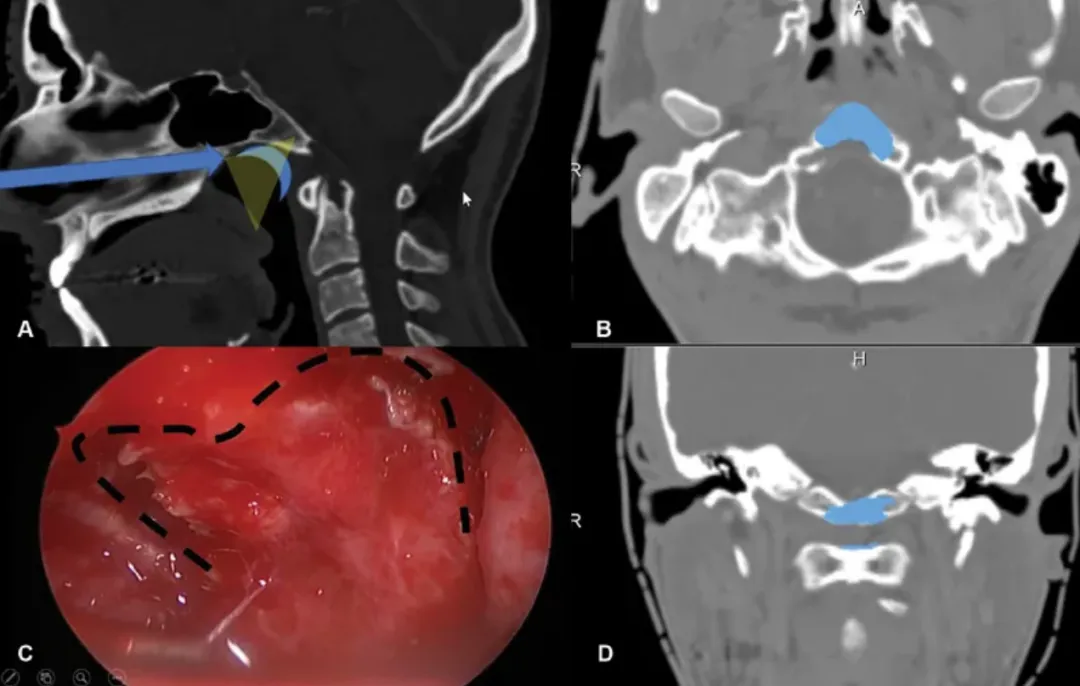

术中通过磁共振成像(MRI)监测术后神经功能缺损和术后肿瘤体积。在鼻内镜下以30度和45度角行双鼻孔入路。随后,制作一个心形皮瓣,钻取斜坡以暴露病变(图2)。在初始减压后,轻轻钻取C1环以到达齿状突内及周围的肿瘤,并进行完全切除。

内镜鼻内入路手术技术示意图。(A)显示手术路径(蓝色箭头),以及在鼻咽上部(蓝月牙)形成的心形皮瓣的位置。这张图强调了需要有角度的内窥镜进行更好的术中视野暴露(黄色半透明三角形)(B)为轴向视图,(C)显示了为获得心形皮瓣而进行的切口的术中内窥镜视图,如本例中所用,(D)为冠状视图。(B和D)显示了术后图像分析的结果,在此过程中,Froelich教授对进行骨磨除的部位进行了分段(蓝色),并将其投影到患者的术前CT扫描上。注意,除了下斜坡外,C1环的上部分也被轻微钻孔以到达齿状突的肿瘤。